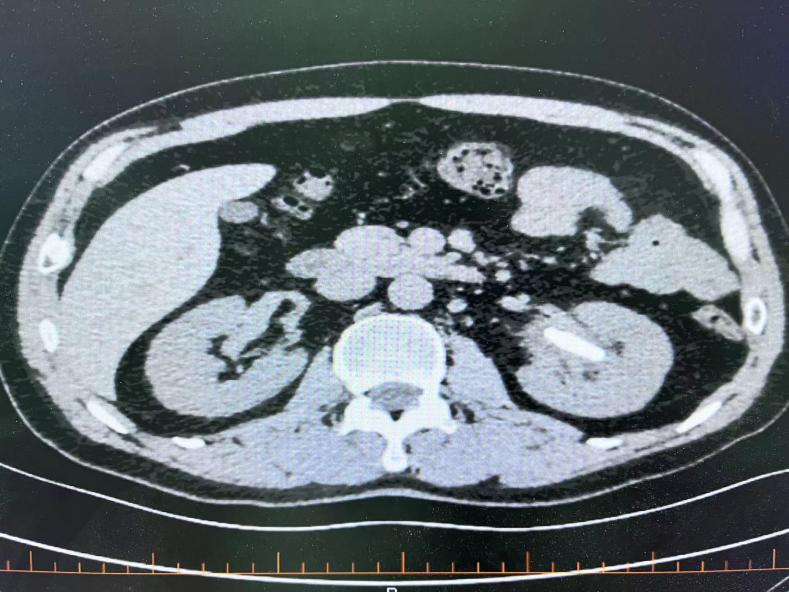

患者术前CT如下: